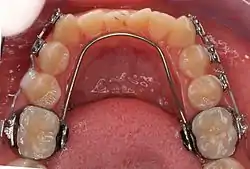

Lower removable lingual arch.

LLA and TPA are fabricated by placing bands on the molars. These are connected to the archwire. The wire can be soldered to the bands or inserted into lingual sheaths welded to the molar band (removable LLA and TPA).